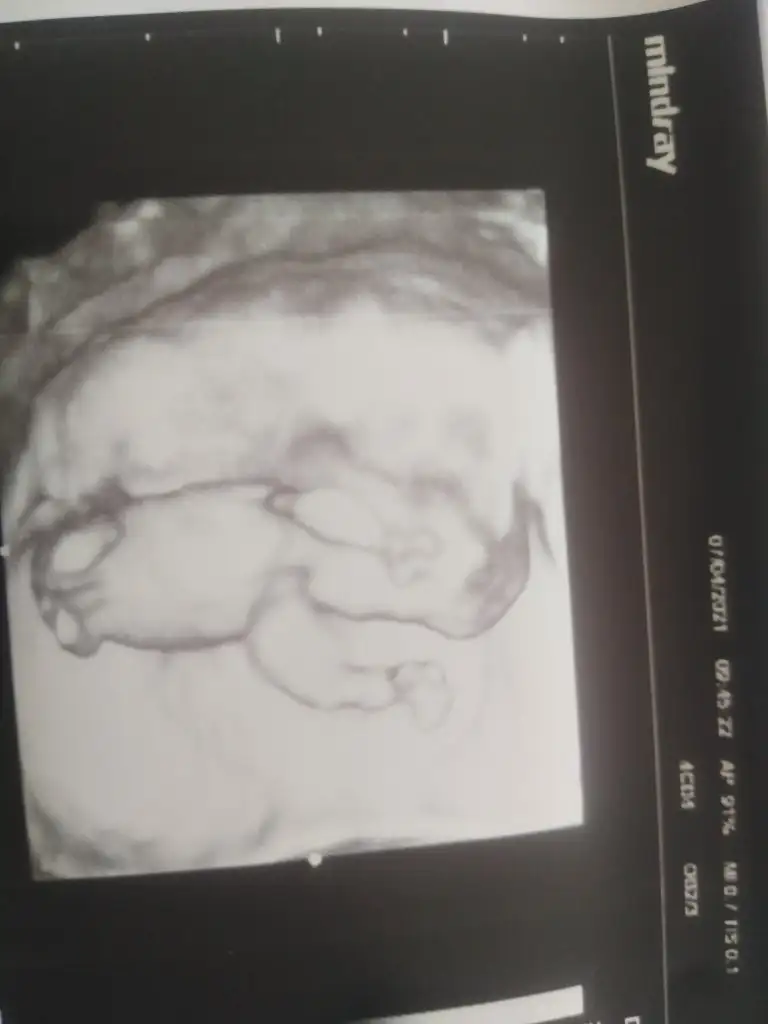

Canım Ikra meyra Ikra meyra bu ultrasona da bakar mısın cok merak ediyoruz bi yakınımızın😇 12.haftada

• 0348DA3E-1526-4C95-845A-A221E6980DCA.webp